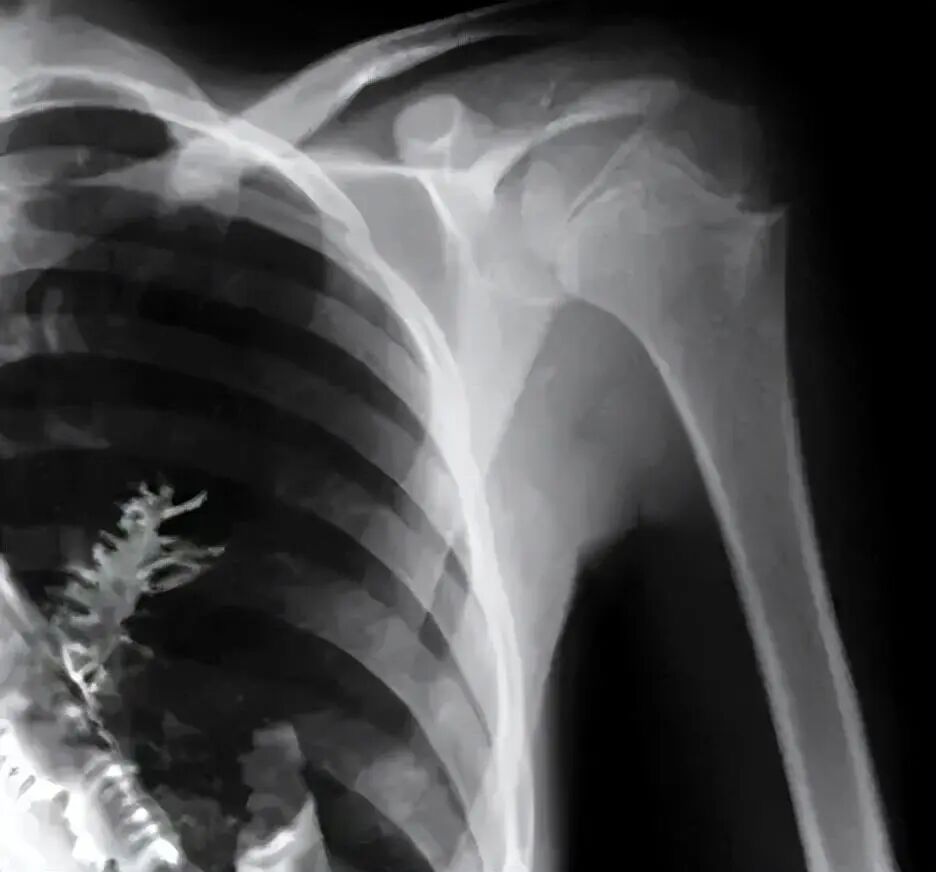

无独有偶,2010年,自马萨诸塞州的 75 岁男子也因为不停咳嗽,呼吸难受叫了救护车,就医后拍摄了X光片,结果显示,肺部有一个小斑点,初步诊断癌症。

矛盾的是,癌症相关的其他检测却表明他未患有癌症。

究竟是怎么回事呢?经过再三检查,最终在肺部发现了一棵正在发芽的豌豆,植株长约1.25cm,手术移除后,男子也恢复了健康,手术后的第一顿,他依然吃的是豌豆。